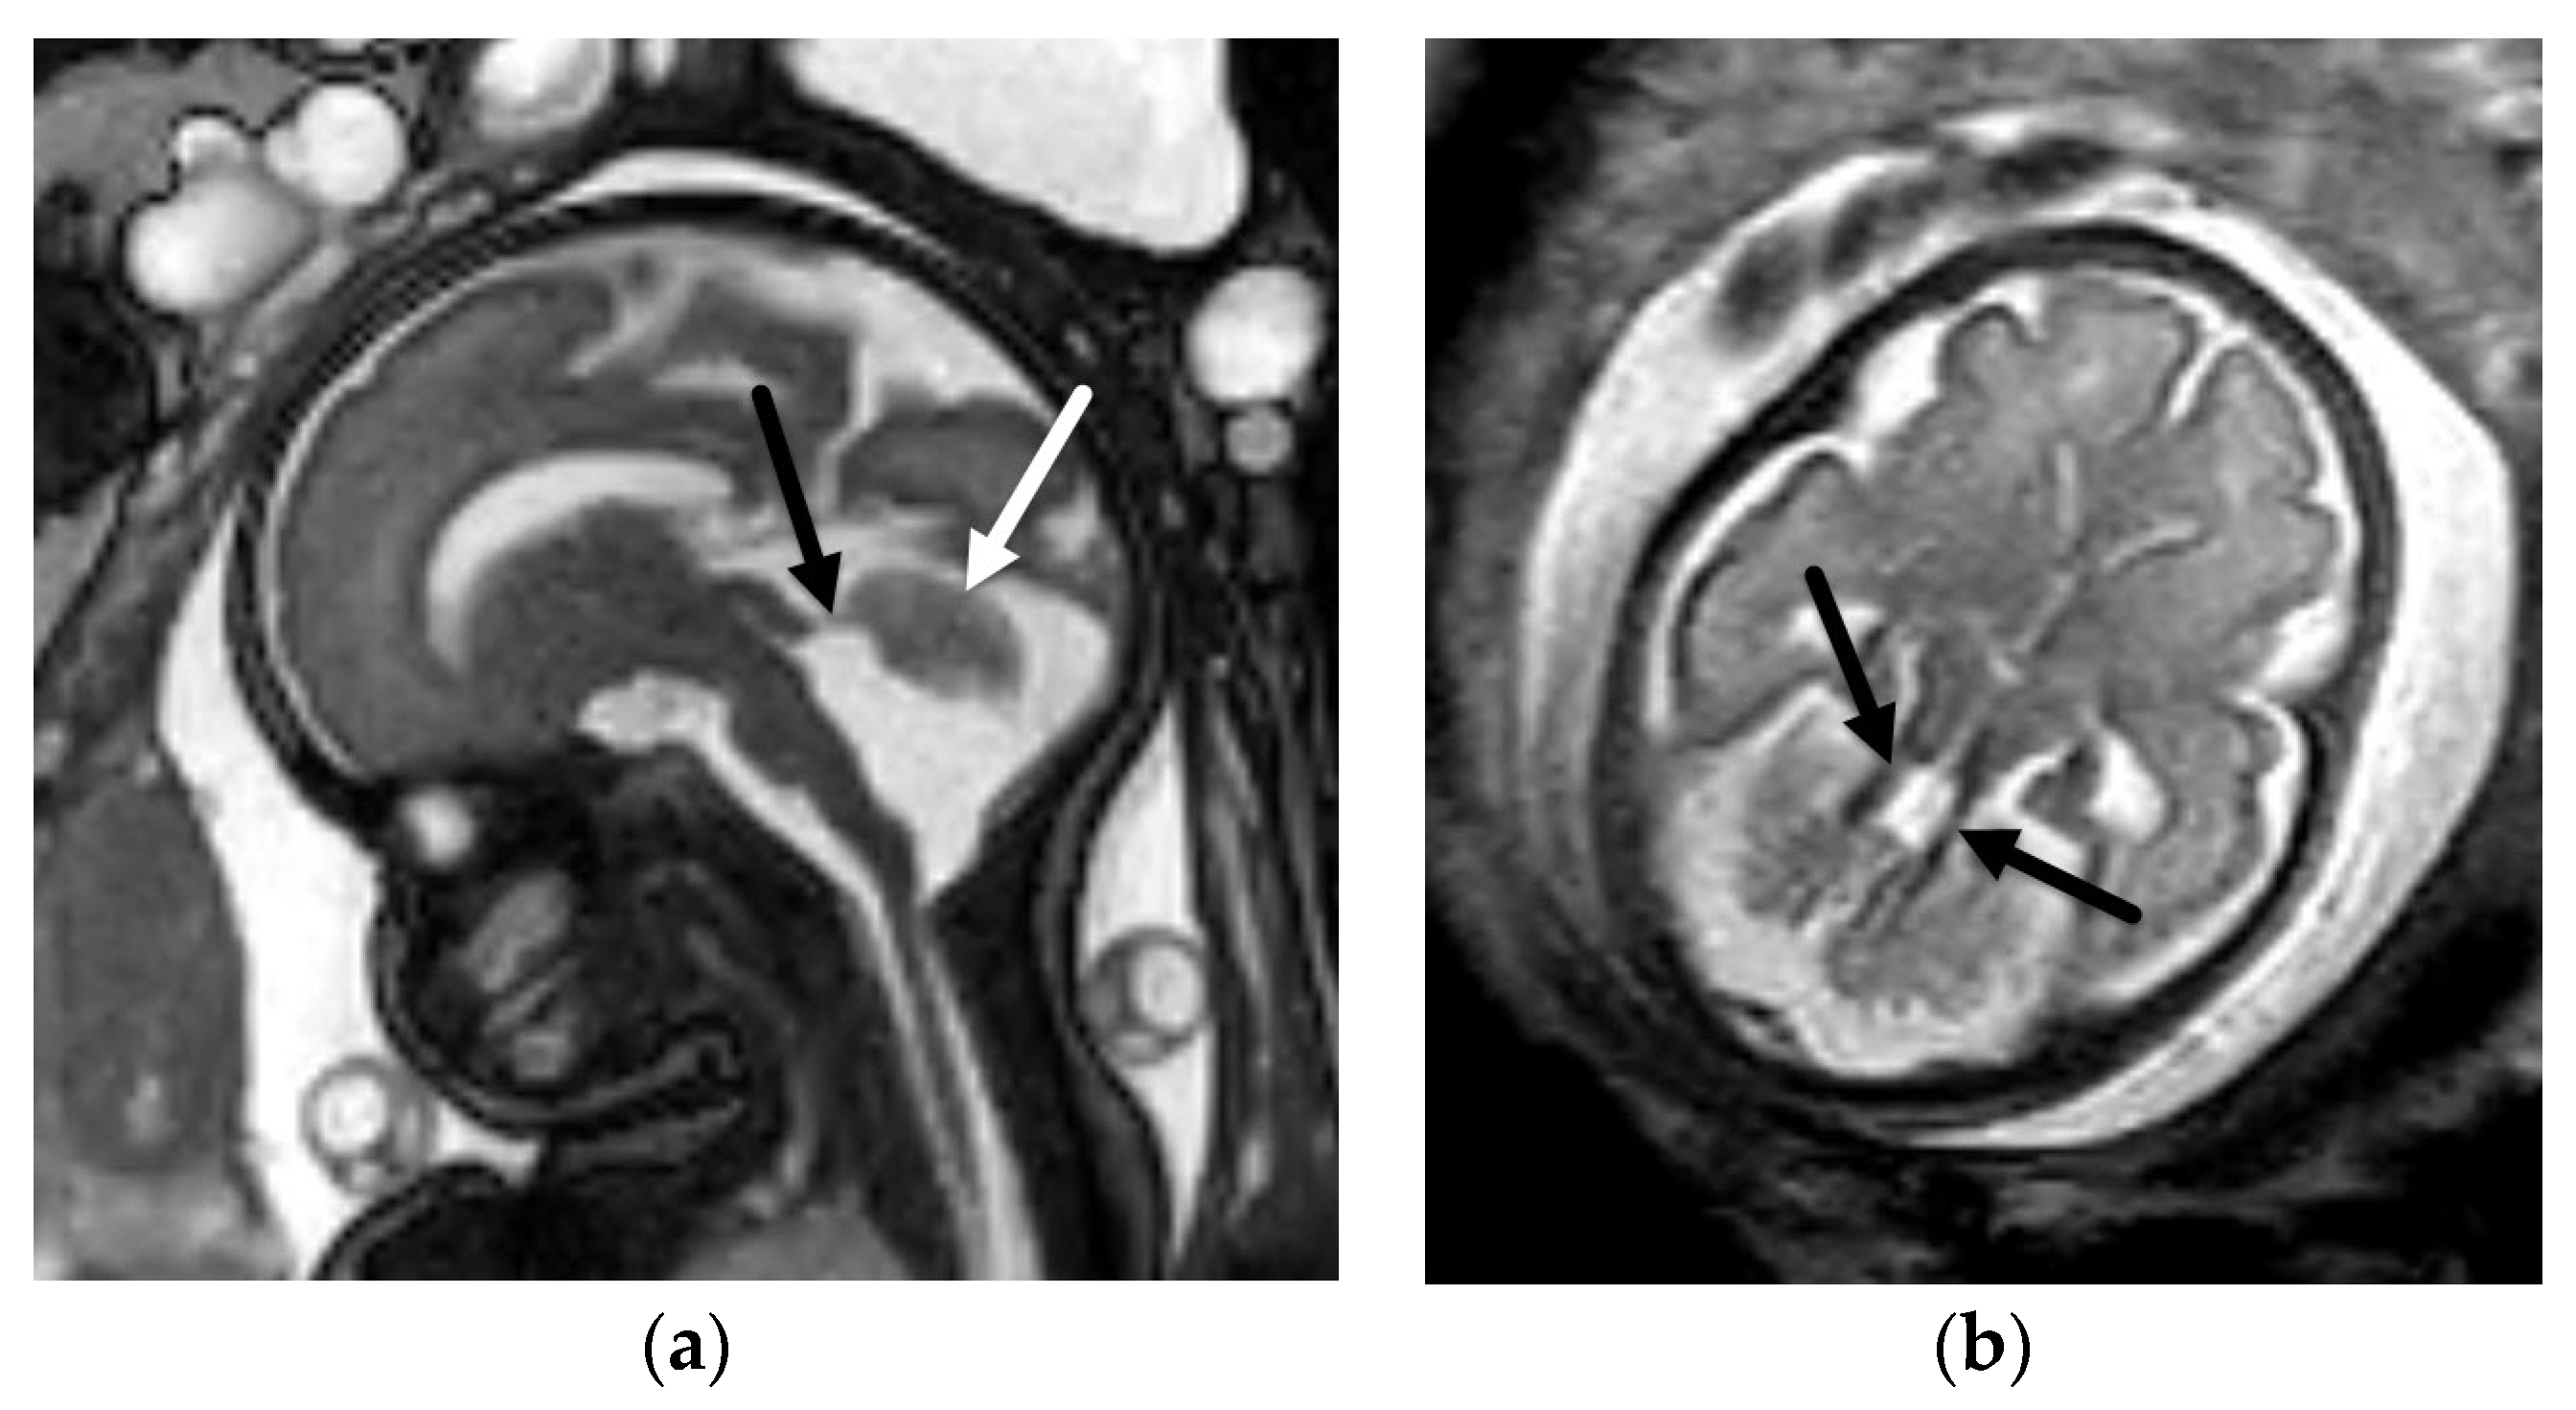

5.1. Dandy-Walker Continuum

- Venkatesan, C.; Kline-Fath, B.; Horn, P.S.; Poisson, K.E.; Hopkin, R.; Nagaraj, U.D. Short- and Long-Term Outcomes of Prenatally Diagnosed Dandy-Walker Malformation, Vermian Hypoplasia, and Blake Pouch Cyst. J. Child Neurol. 2021, 36, 1111–1119. [Google Scholar] [CrossRef]

- Kollias, S.S.; Ball, W.S.; Prenger, E.C. Cystic malformations of the posterior fossa: Differential diagnosis clarified through embryologic analysis. Radiographics 1993, 13, 1211–1231. [Google Scholar] [CrossRef]

- Nagaraj, U.D.; Kline-Fath, B.M.; Horn, P.S.; Venkatesan, C. Evaluation of Posterior Fossa Biometric Measurements on Fetal MRI in the Evaluation of Dandy-Walker Continuum. AJNR Am. J. Neuroradiol. 2021, 42, 1716–1721. [Google Scholar] [CrossRef] [PubMed]

- Robinson, A.J.; Ederies, M.A. Seminars in Fetal & Neonatal Medicine Diagnostic imaging of posterior fossa anomalies in the fetus. Semin. Fetal Neonatal Med. 2016, 21, 312–320. [Google Scholar] [PubMed]

- Nagaraj, U.D.; Kline-Fath, B.M.; Calvo-Garcia, M.A.; Vadivelu, S.; Venkatesan, C. Fetal and postnatal MRI findings of Blake pouch remnant causing obstructive hydrocephalus. Radiol. Case Rep. 2020, 15, 2535–2539. [Google Scholar] [CrossRef]